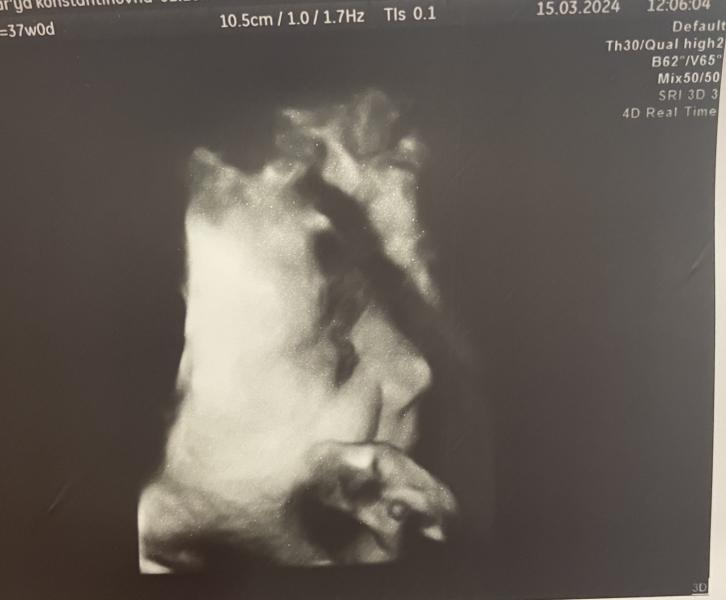

Боже современное узи это просто какое-то чудо.. вчера была на предродовом узи и врач показала сына в 4Д, мое сердце просто растаяло от папиного носа, хомячих щечек и маленьких пальчиков. А уж фото демонстрирующее вокальные возможности это вообще разрыв 😅

Поскорее бы с вами встретиться молодой человек ❤️